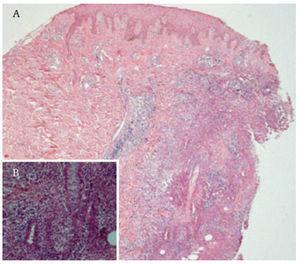

Reporte del casoSe trata de una mujer de 52 años con diagnóstico de CU de 10 años de evolución. Como única manifestación extraintestinal presentaba artritis periférica. Debido a la presencia de displasia de alto grado en biopsia obtenida por colonoscopia, fue sometida a una proctocolectomia con reservorio ileoanal e ileostomía en asa. El periodo posoperatorio de la paciente transcurrió sin complicaciones y se egresó a los cinco días. Seis semanas después de la cirugía, la paciente refirió un dolor intenso en el área periostomal. A la exploración se observó una gran úlcera que rodeaba el estoma con secreción purulenta y necrosis en los bordes (figura 1). Ésta se trató inicialmente como una falla en el manejo del estoma con dermatitis de contacto y una infección agregada. La paciente recibió tratamiento con antibióticos orales y capacitación en el manejo de estoma. Después de dos semanas, la lesión empeoró y apareció una nueva úlcera en la región escapular derecha de iguales características, pero más pequeña (figura 2). El diagnóstico se realizó por medio de una biopsia. En el estudio histopatológico de la piel periostomal se observó inflamación aguda y crónica en la dermis y en el tejido adiposo (HE-40X) (figura 2). También se observaron abscesos y vasculitis, así como migración de polimorfonucleares hacia la pared vascular (125X). Los cultivos de las biopsias no desarrollaron colonias. La paciente no tenía evidencia de enfermedad intestinal activa. El tratamiento se realizó con 40 mg al día de prednisona orales y con cuidados locales de la úlcera, incluyendo debridación bajo anestesia local. Las úlceras cicatrizaron a los seis meses de tratamiento y al año no presentó recurrencia.

Figura 1. Pioderma gangrenoso periostomal.